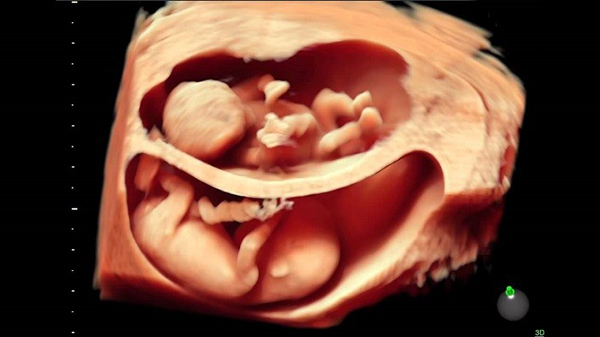

Thai nhi 37 tuần tuổi đã bước vào giai đoạn quan trọng, chuẩn bị ra đời. Lúc này thai đã có khả năng dần thích nghi với môi trường bên ngoài bụng mẹ.. Trong thời gian từ tuần 32 trở đi, mẹ bầu cần chú ý thăm khám thường xuyên hơn để theo dõi tình hình thai nhi cũng như dự tính thời điểm sinh chính xác nhất.